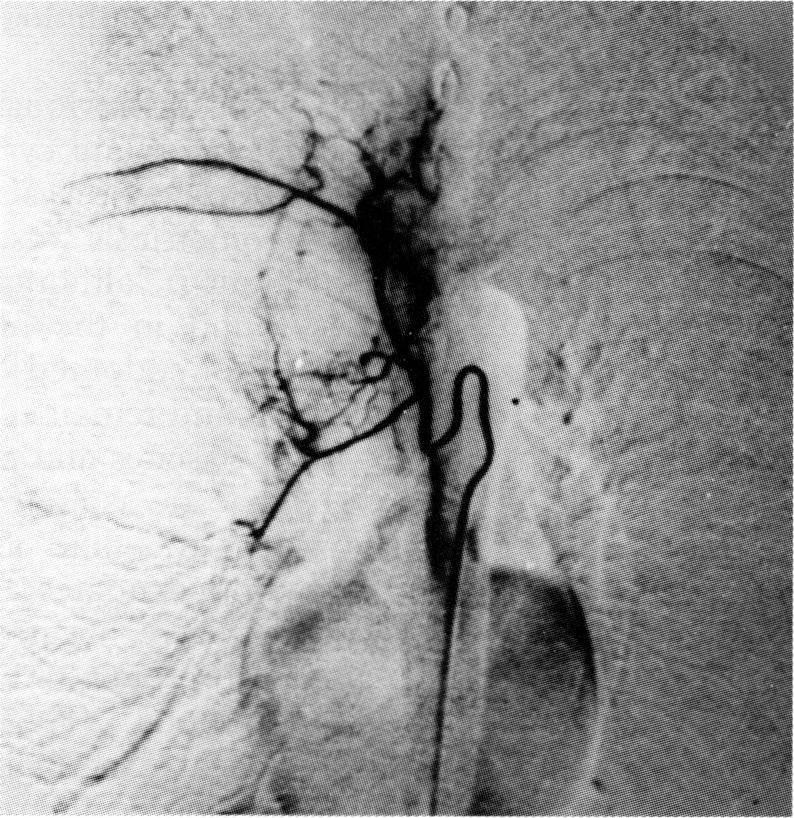

The case is described of a 31 year old woman who presented with complaints of recurrent haemoptysis coinciding with menstruation. Bronchoscopic examination revealed multiple purplish-red submucosal lesions on the right side of the trachea and bilateral bronchial trees which appeared during her menses and regressed in the intermenstrual periods. Brush cytology revealed cell clusters consistent with endometrial origin. Bronchial angiography demonstrated prominent vasculature at the right paratracheal area and bilateral bronchial trees corresponding to the lesions seen on bronchoscopic examination. Her haemoptysis was satisfactorily controlled by danazol therapy and follow up bronchoscopy showed disappearance of the tracheobronchial lesions. To our knowledge this is the first case of thoracic endometriosis with tracheal involvement.

本文描述了一名31岁女性,她因反复咯血就诊,咯血与月经周期相符。支气管镜检查发现气管右侧及双侧支气管树有多个紫红色黏膜下病变,这些病变在月经期出现,在月经间期消退。刷检细胞学检查发现细胞团块符合子宫内膜来源。支气管血管造影显示右气管旁区域及双侧支气管树有明显的血管,与支气管镜检查所见病变相对应。达那唑治疗使她的咯血得到了满意控制,随访支气管镜检查显示气管支气管病变消失。据我们所知,这是首例累及气管的胸段子宫内膜异位症病例。